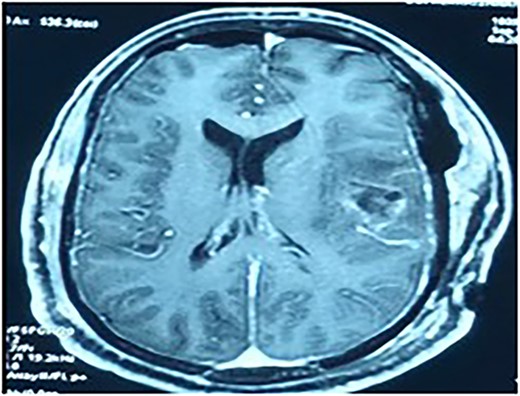

In view of the location of the lesion and the involvement of the speech area, an awake craniotomy was planned for resection of the lesion. The goal of the surgery was maximal safe resection with function preservation. The patient was positioned in the supine position, with the patient’s head fixed with a three-pin holder (Fig. 4), and ultrasound was used to localize the lesion before opening the dura. The lesion was identified and microsurgical gross total resection (Fig. 5) was completed by using speech mapping techniques. Post-procedure, the patient had intact speech and had no new onset deficits.

The patient was positioned in the supine position, with the head fixed with a three-pin holder.